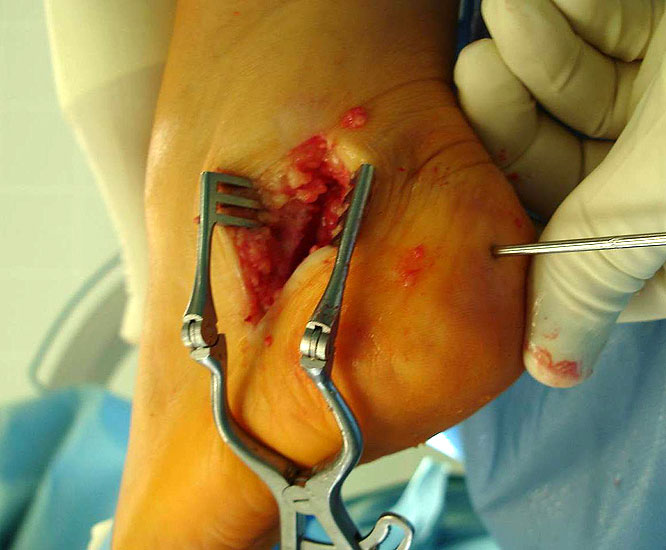

715.<br> Für die medialisierende Calcaneusosteotomie wird ein bogenförmiger Hautschnitt in Höhe des hinteren Fersenbeines gesetzt, die Subcutis bis zum Fersenbein durchtrennt und dieser bogenförmige Lappen nach ventral präpariert. Dadurch kommt es zu einem Schutz des Nervus suralis, welcher gemeinsam mit den Peronealsehnen nach vorne gehalten wird.<br> Es wird nun das Fersenbein mit einem Wundspreizer eingestellt und cranial sowie caudal mit 2 Hohmannhaken umfahren.<br> Dann wird das Fersenbein mit der oszillierenden Säge osteotomiert, mit dem Meißel und dem Wundspreizer distrahiert.<br> Danach wird das Fersenbein ca. 1 cm nach medial verschoben, unter Vermeidung der Cranialisierung des hinteren Calcaneus . Dann wird von dorsal über eine Hautstichincision der Bohrdraht für die 4,5mm (- 6,5 mm) kanülierte Schraube eingebracht und über die Osteotomie in den vorderen Calcaneusanteil vorgeschoben.<br> Kontrolle im Bildwandler in 2 Ebenen. Wenn die Bohrdrahtlage gut ist Überbohren für die kanülierten Schrauben und Eindrehen der Schraube. (Alternativ kann an Stelle der Schraubentechnik auch eine Fixation mit Stufenplatten oder Ähnlichem verwendet werden).<br> Wundverschluss am lateralen Zugang und über der Stichincision.</p>"> 715.<br> Für die medialisierende Calcaneusosteotomie wird ein bogenförmiger Hautschnitt in Höhe des hinteren Fersenbeines gesetzt, die Subcutis bis zum Fersenbein durchtrennt und dieser bogenförmige Lappen nach ventral präpariert. Dadurch kommt es zu einem Schutz des Nervus suralis, welcher gemeinsam mit den Peronealsehnen nach vorne gehalten wird.<br> Es wird nun das Fersenbein mit einem Wundspreizer eingestellt und cranial sowie caudal mit 2 Hohmannhaken umfahren.<br> Dann wird das Fersenbein mit der oszillierenden Säge osteotomiert, mit dem Meißel und dem Wundspreizer distrahiert.<br> Danach wird das Fersenbein ca. 1 cm nach medial verschoben, unter Vermeidung der Cranialisierung des hinteren Calcaneus . Dann wird von dorsal über eine Hautstichincision der Bohrdraht für die 4,5mm (- 6,5 mm) kanülierte Schraube eingebracht und über die Osteotomie in den vorderen Calcaneusanteil vorgeschoben.<br> Kontrolle im Bildwandler in 2 Ebenen. Wenn die Bohrdrahtlage gut ist Überbohren für die kanülierten Schrauben und Eindrehen der Schraube. (Alternativ kann an Stelle der Schraubentechnik auch eine Fixation mit Stufenplatten oder Ähnlichem verwendet werden).<br> Wundverschluss am lateralen Zugang und über der Stichincision.</p>" srcset="/assets/images/a/3-raswd6qgkh6s353.jpg 1x, /assets/images/g/3-exngvjjv83x827d.jpg 1.5x, /assets/images/w/3-836r57qt8j3eh0w.jpg 2x" width="270" height="240" loading="lazy">

Abbildung 3

Abbildung 4